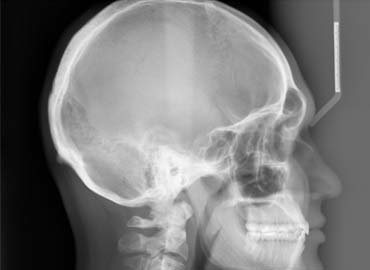

Cephalometric X-rays

A cephalometric X-ray, which is also sometimes referred to simply as a ceph, is a diagnostic radiograph used primarily for orthodontic treatment planning. A cephalometric x-ray is taken during the orthodontic records appointment.

Cephalometric X-rays are also used by otolaryngologists—doctors who specialize in the treatment of ear, nose, and throat (ENT) disorders such as sleep apnea—because these X-rays provide a view of the patient’s airways. The process of undergoing a cephalometric X-ray is pretty straightforward. Concentrating on the patient’s profile—or side view of the head—the x-ray technician positions the patient according to specific criteria necessary when taking a cephalometric X-ray.

The exposure takes approximately 10 seconds and the X-ray is developed in approximately five to six minutes. Most dental offices are equipped with the equipment necessary to take a cephalometric X-ray.